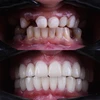

Zirkonyum uygulamalar

Porselen uygulamaları

Laminate veneer